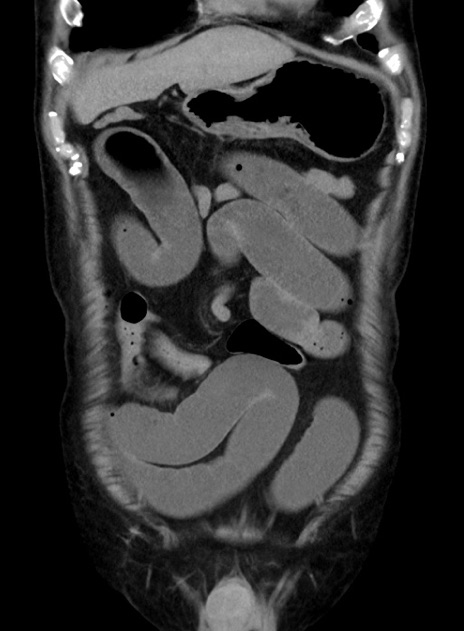

横断像

【症例】70歳代 男性

【主訴】腹痛・嘔吐

【現病歴】昨晩より、嘔吐・腹痛あり。今朝になっても嘔吐あり。来院。

【既往歴】心臓バイパス手術、開腹胆摘、腸閉塞

【身体所見】BP 107/71mmHg、HR 116/min、腹部:平坦、軟、下腹部に軽度圧痛あり。反跳痛なし。

【データ】WBC 15100、CRP 0.32